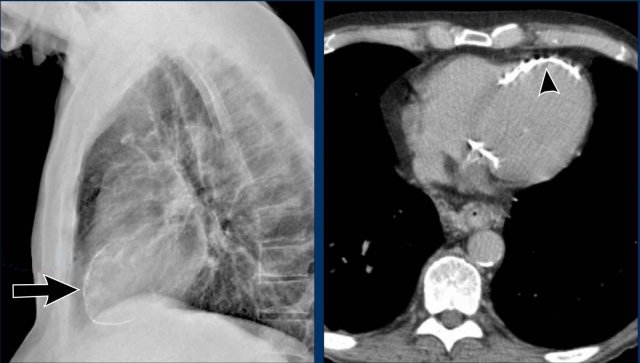

Postoperative Pericardial Hemorrhage

In patients with recent cardiac surgery, a sudden change in heart size on chest X-ray should raise suspicion for pericardial bleeding, which may be life-threatening.

Case Example 2:

• A postoperative patient showed a change in the cardiac silhouette.

Case Example 2 - CT imaging

• CT imaging revealed a large posterior pericardial effusion compressing the left ventricle (blue arrow: effusion; red arrow: compressed, contrast-filled left ventricle).

• Surgical exploration confirmed a large posterior pericardial hematoma.

Note

: Minimal anterior fluid on ultrasound may underestimate the true volume if the effusion is loculated posteriorly, highlighting the value of CT in postoperative cases.

Especially in patients who had recent cardiac surgery an enlargement of the heart figure can indicate pericardial bleeding.

This patient had a change in the heart configuration (importance of prior imaging) and pericardial bleeding was suspected.

Ultrasound demonstrated only a minimal pericardial effusion.